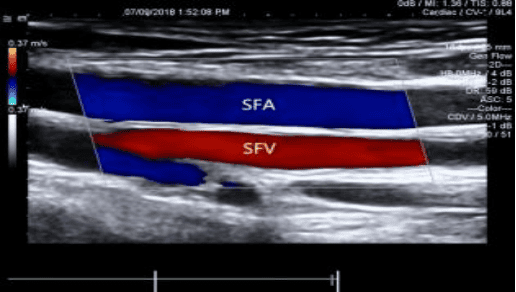

3、血管亚专业组:全面开展了颈动脉、四肢血管、肾动静脉、腹部血管等全身血管彩色多普勒检查项目,可准确评估颈部动脉狭窄程度及斑块稳定性、血管置管术后评估、血液透析人工动静脉瘘的术前及术后评估、皮瓣移植术前评估等等。为临床提供大量有价值的诊断信息。